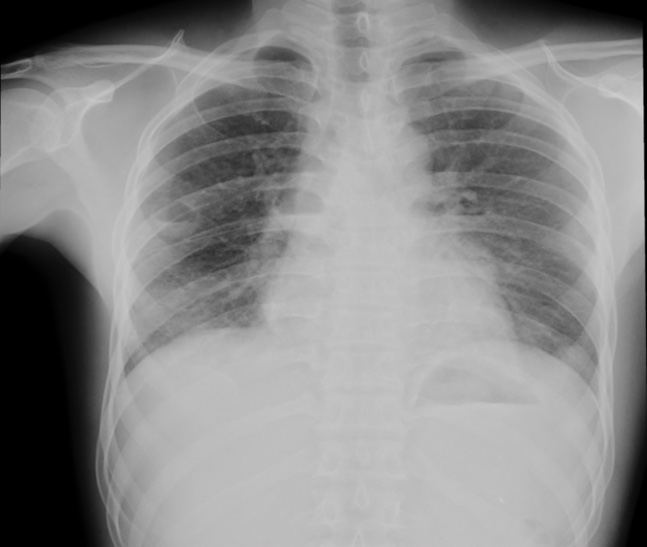

ภาพรังสีทรวงอก

อาศัยการซักประวัติการกินปูหรือกุ้งที่ปรุงไม่สุก การตรวจพบไข่พยาธิใบไม้ปอดในเสมหะ (sputum fresh smear) หรือในอุจจาระทำให้วินิจฉัยโรคได้ โดยจะมีโอกาสพบได้มากขึ้นถ้าทำการตรวจหลายครั้ง โดยไข่พยาธิจะมีสีน้ำตาลทองรูปยาวรีขนาดประมาณ 68-118 ไมครอน x 39-67 ไมครอน ใน Paragonimus heterotremus จะมีเปลือกหนาสม่ำเสมอตลอด ส่วน Paragonimus westermani เปลือกไข่ส่วนตรงข้ามกับฝา (operculum) จะหนากว่าส่วนอื่นๆ การตรวจอื่นๆ ได้แก่ การตรวจเลือดโดยใช้วิธี immunoblot assay โดยการใช้เอนติเจนจากตัวพยาธิ การทำ skin test เป็นต้น การตรวจ pleural fluid จะพบลักษณะของ exudate ที่มี eosinophil สูง การตรวจภาพรังสีทรวงอกจะพบ nodule, pneumothorax, interstitial opacities, cavity, ring cyst ลักษณะคล้าย bronchiectasis ได้8,9 ส่วน pleural effusion พบได้ประมาณร้อยละ 48 ถึง 624,10 ผู้ป่วยประมาณร้อยละ 10 ถึง 20 มีภาพรังสีทรวงอกปกติได้11 ภาพรังสีคอมพิวเตอร์พบ parenchymal consolidation ในผู้ป่วยส่วนใหญ่ linear streak พบได้ร้อยละ 3 ถึง 412 พบ ring shadow ได้ ประกอบด้วย cyst ที่มีพยาธิอยู่ติดกับผนังของ cyst7 และอาจพบ pleural nodule ได้